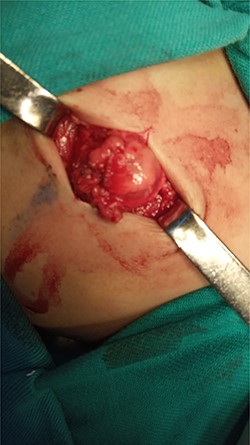

After studying the case, we decided to perform primary repair of the abdominal wall defect without meshplasty since the diameter of the aperture was <5 cm. An oblique left lumbar incision was performed above the hernia, revealing a defect measuring 4 cm in diameter in the upper lumbar triangle. Dissection of the peritoneum and hernial sac was performed starting from the margins of abdominal muscles (Fig. 4), the hernial sac was internally reduced and the muscular margins were closed by simple continuous sutures made from prolene 0 (Fig. 5). Complete closure of the defect was confirmed and a draining tube was inserted subcutaneously before closing the skin. The drain was removed after 2 days; the stitches were removed after 10 days. The patient was faring well after the surgery. Recurrence of the hernia was not reported. We recommended that the patient should be followed up by an orthopedist for the correction of disability, which is caused by LCVS.

The consolidation stage after reduction of the hernia sac of the abdominal cavity.